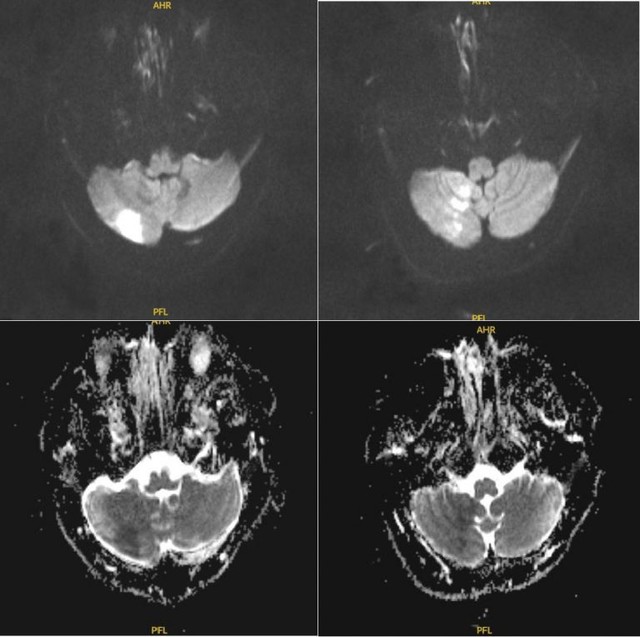

Ngay lập tức, người bệnh được tiến hành chụp MRI, kết quả xác định có vùng nhồi máu tiểu não bên phải.

Hình chụp MRI của bệnh nhân trong khi đá banh bị đột quỵ. Ảnh: BVCC